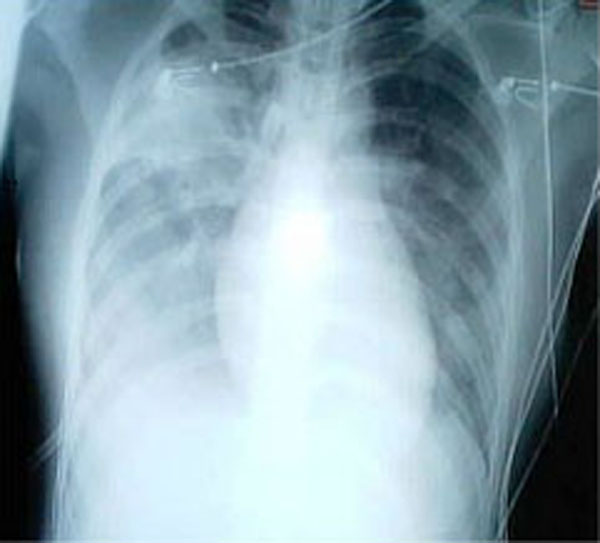

Three common patterns of pneumonia may be detected on chest X-ray which include:

- Lobar pneumonia

Lobar Pneumonia

Lobar pneumonia is characterized by the consolidation of a whole lung lobe.

Lobar pneumonia is typically caused by bacteria which include:

- Streptococcus pneumonia (95 percent)

- Klebsiella pneumonia

Typical gross lobar pneumonia presents in phases:

- Congestion resulting from edema and clogged vessels

- Exudate, neutrophils, and hemorrhage cause red hepatization, which gives the typically spongy lung a solid consistency by filling the alveolar air spaces

- Gray hepatization as a result of red blood cell (RBC) breakdown in the exudate